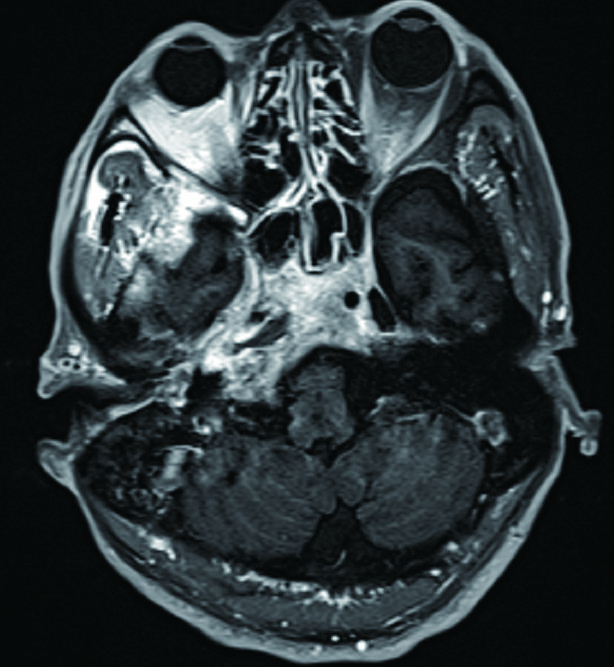

病例1,患者男性,66岁,因头痛3周,复视1周入院。患者3周前起右侧太阳穴针刺样疼痛,影响睡眠。2周前出现咽痛鼻塞流涕及双耳听力下降,伴有右侧额部皮肤红疹,上述症状在当地医院治疗后减轻。1周前出现复视,当地医院治疗后症状无好转,诊断:颅内感染,多颅神经麻痹转来本院急诊。查体:神清,面部可见散在淡色丘疹,以右侧前额为主,右眼外展受限,面部痛触觉无殊,四肢肌力5级,病理反射阴性。脑脊液生化常规示:潘氏试验阳性,有核细胞970/μL;血沉28.00 mm/h,C反应蛋白14.1 mg/L。增强头颅MR提示两侧海绵窦增粗增宽,考虑炎症,并见双侧筛窦上颌窦蝶窦炎(图 1)。予头孢曲松钠2.0 g静脉注射抗感染治疗。治疗2周后头痛明显减轻,但复视症状无好转。复查血常规正常,C反应蛋白正常范围,血沉28.00 mm/h,脑脊液生化及常规正常范围。复查头颅增强MR提示病变范围较前无缩小。鼻窦CT提示双侧蝶窦炎症较前加重(图 2)。建议患者行鼻内镜下蝶窦手术。患者自觉症状减轻拒绝手术,要求出院。出院后在外院继续头孢曲松钠抗感染治疗。治疗10 d后因头痛复视症状无改善,并出现面颊部感觉减退再次入院。入院后查血常规,C反应蛋白正常,血沉28.00 mm/h,脑脊液潘氏试验阳性,细胞数量继续减少至60/μL。继续抗感染治疗。再次头颅MR及鼻窦CT复查提示海绵窦及蝶窦内病变较前范围增大(图 3),经多学科讨论,转本科行视频内镜下双侧蝶窦开放术。术后第三天鼻腔填塞物完全抽除后头痛症状明显缓解,术后6 d出院,头痛症状消失,复视仍存,出院后继续抗感染治疗,定期门诊复诊,术后6个月,复视症状消失。

图 1 双侧海绵窦增宽,右侧明显